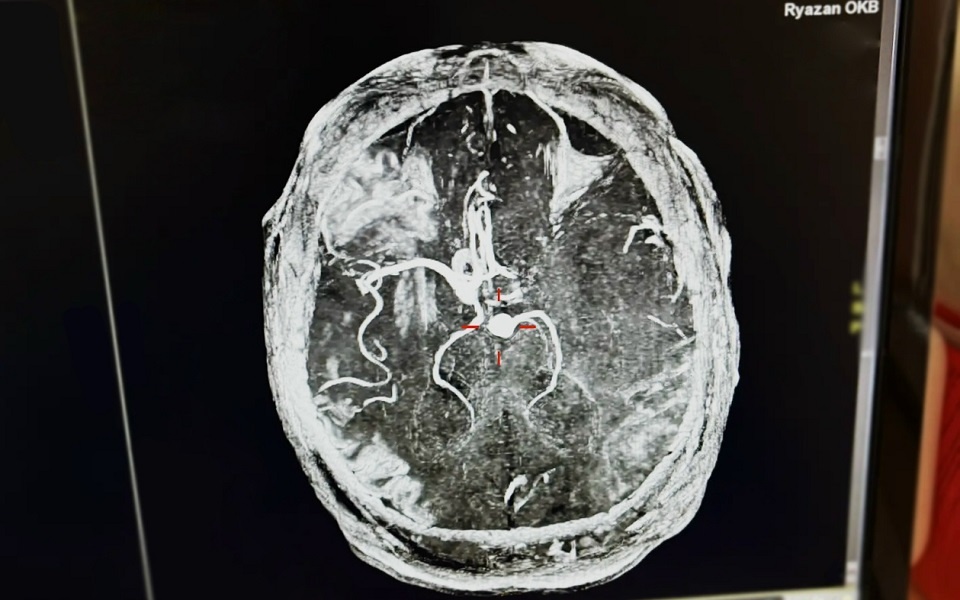

Рязанские врачи спасли 43-летнего рязанца с инсультом. О сложном случае рассказали представители минздрава региона. Скорую помощь вызвала жена пациента - у него внезапно отнялась половина тела. Врачи оперативно доставили мужчину в ОКБ. "Ему измерили давление, и результаты оказались шокирующими — 265/155, что свидетельствовало об опасном гипертоническом кризе", - рассказали в минздраве. Диагностировали инсульт. Тромб сумели устранить, а когда начали выяснять, что могло привести к развитию инсульта, поначалу не обнаружили типичных причин: пациент не пил и не курил, не имел предрасположенности или патологий. Затем жена рассказала о его привычке выпивать ежедневно 7-8 банок энергетических напитков. Муж говорил, что ему нравится их вкус. Врачи же предостерегают: кофеин в больших дозах в сочетании с дополнительными стимулирующими ингредиентами может привести к росту давления, спазмам сосуда мозга, опасному сердцебиению. Лучше отказаться от таких излишеств, чтобы сохранить здоровье.

Иллюстрации:  минздрав Рязанской области